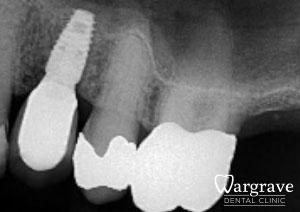

Healthy Smiles These are more advanced examples of different treatments available.All cases shown were carried out by Dr R Khurana unless otherwise stated. Immediate implants Anterior Mandible Bone Regeneration Anterior Mandibular Implant Bridge Maxillary Anterior Implant Bridge Implant stabilised ‘Life Like’ replacement dentures Implant Bridge after 10-years with zero bone loss Implant examples including ZBLC concepts Adhesive Bridge solution for a missing premolar Multidisciplinary care Orthodontics, Replacement veneers and composite bonding Adhesive Bridge solution for missing central incisors Replacement crown, Veneer and Composite Bonding Replacement Crowns and Veneer Injection Moulding using Composite Resin Equilibration Tooth Whitening to treat Developmental Discolouration